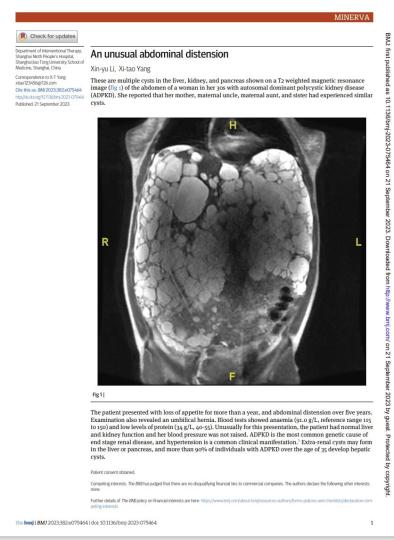

该名女性患者因严重腹胀,活动后即胸闷气促,严重影响日常生活,此前多处就医均未获得可行的药物治疗或外科手术方案。在上海第九人民医院,该名患者被确诊罹患遗传性疾病——常染色体显性多囊肾病(ADPKD)。

据介绍,ADPKD常表现为多囊肾、多囊肝、多囊胰,其临床症状多出现于30岁到40岁患者,常表现为腹痛、腹胀,此外,也可出现高血压、血尿及反复尿路感染等临床症状。如果得不到积极有效治疗,患者可发展为肝肾功能衰竭,危及生命。据统计,近一半的ADPKD患者可能进展为肝肾衰竭。